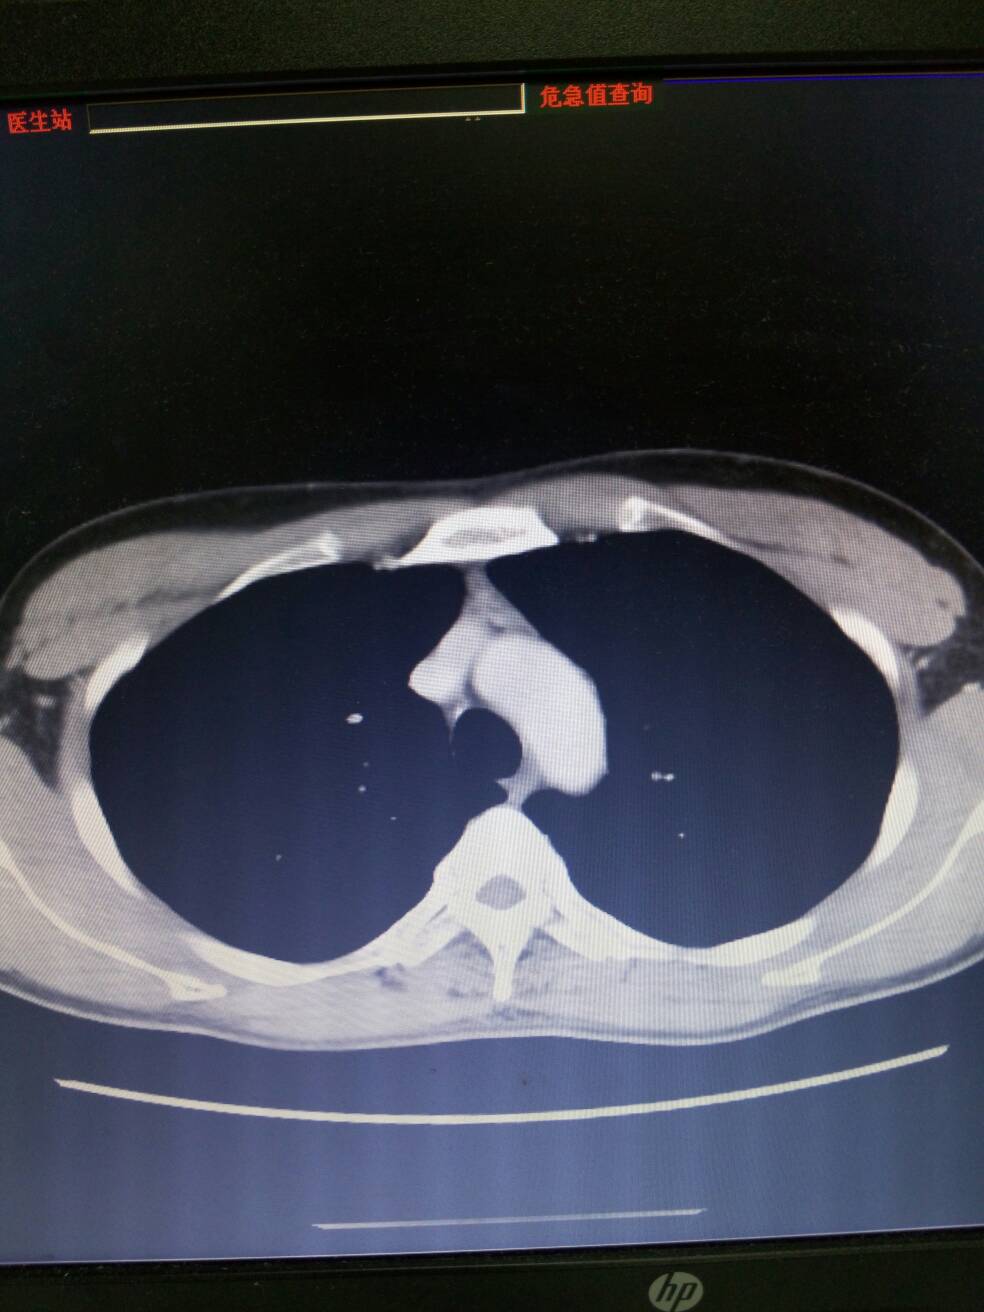

重症肌无力伴胸腺增生。男,29岁,双侧眼睑下垂伴复视20年。查胸部CT增强如图。